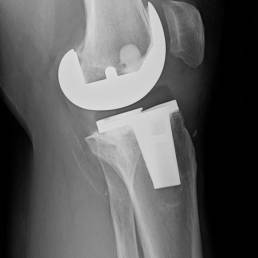

6. Materiales Avanzados:

El desarrollo de nuevos materiales, como aleaciones y polímeros, está facilitando la creación de implantes más duraderos, biocompatibles y con capacidades mejoradas para integrarse con el tejido óseo.